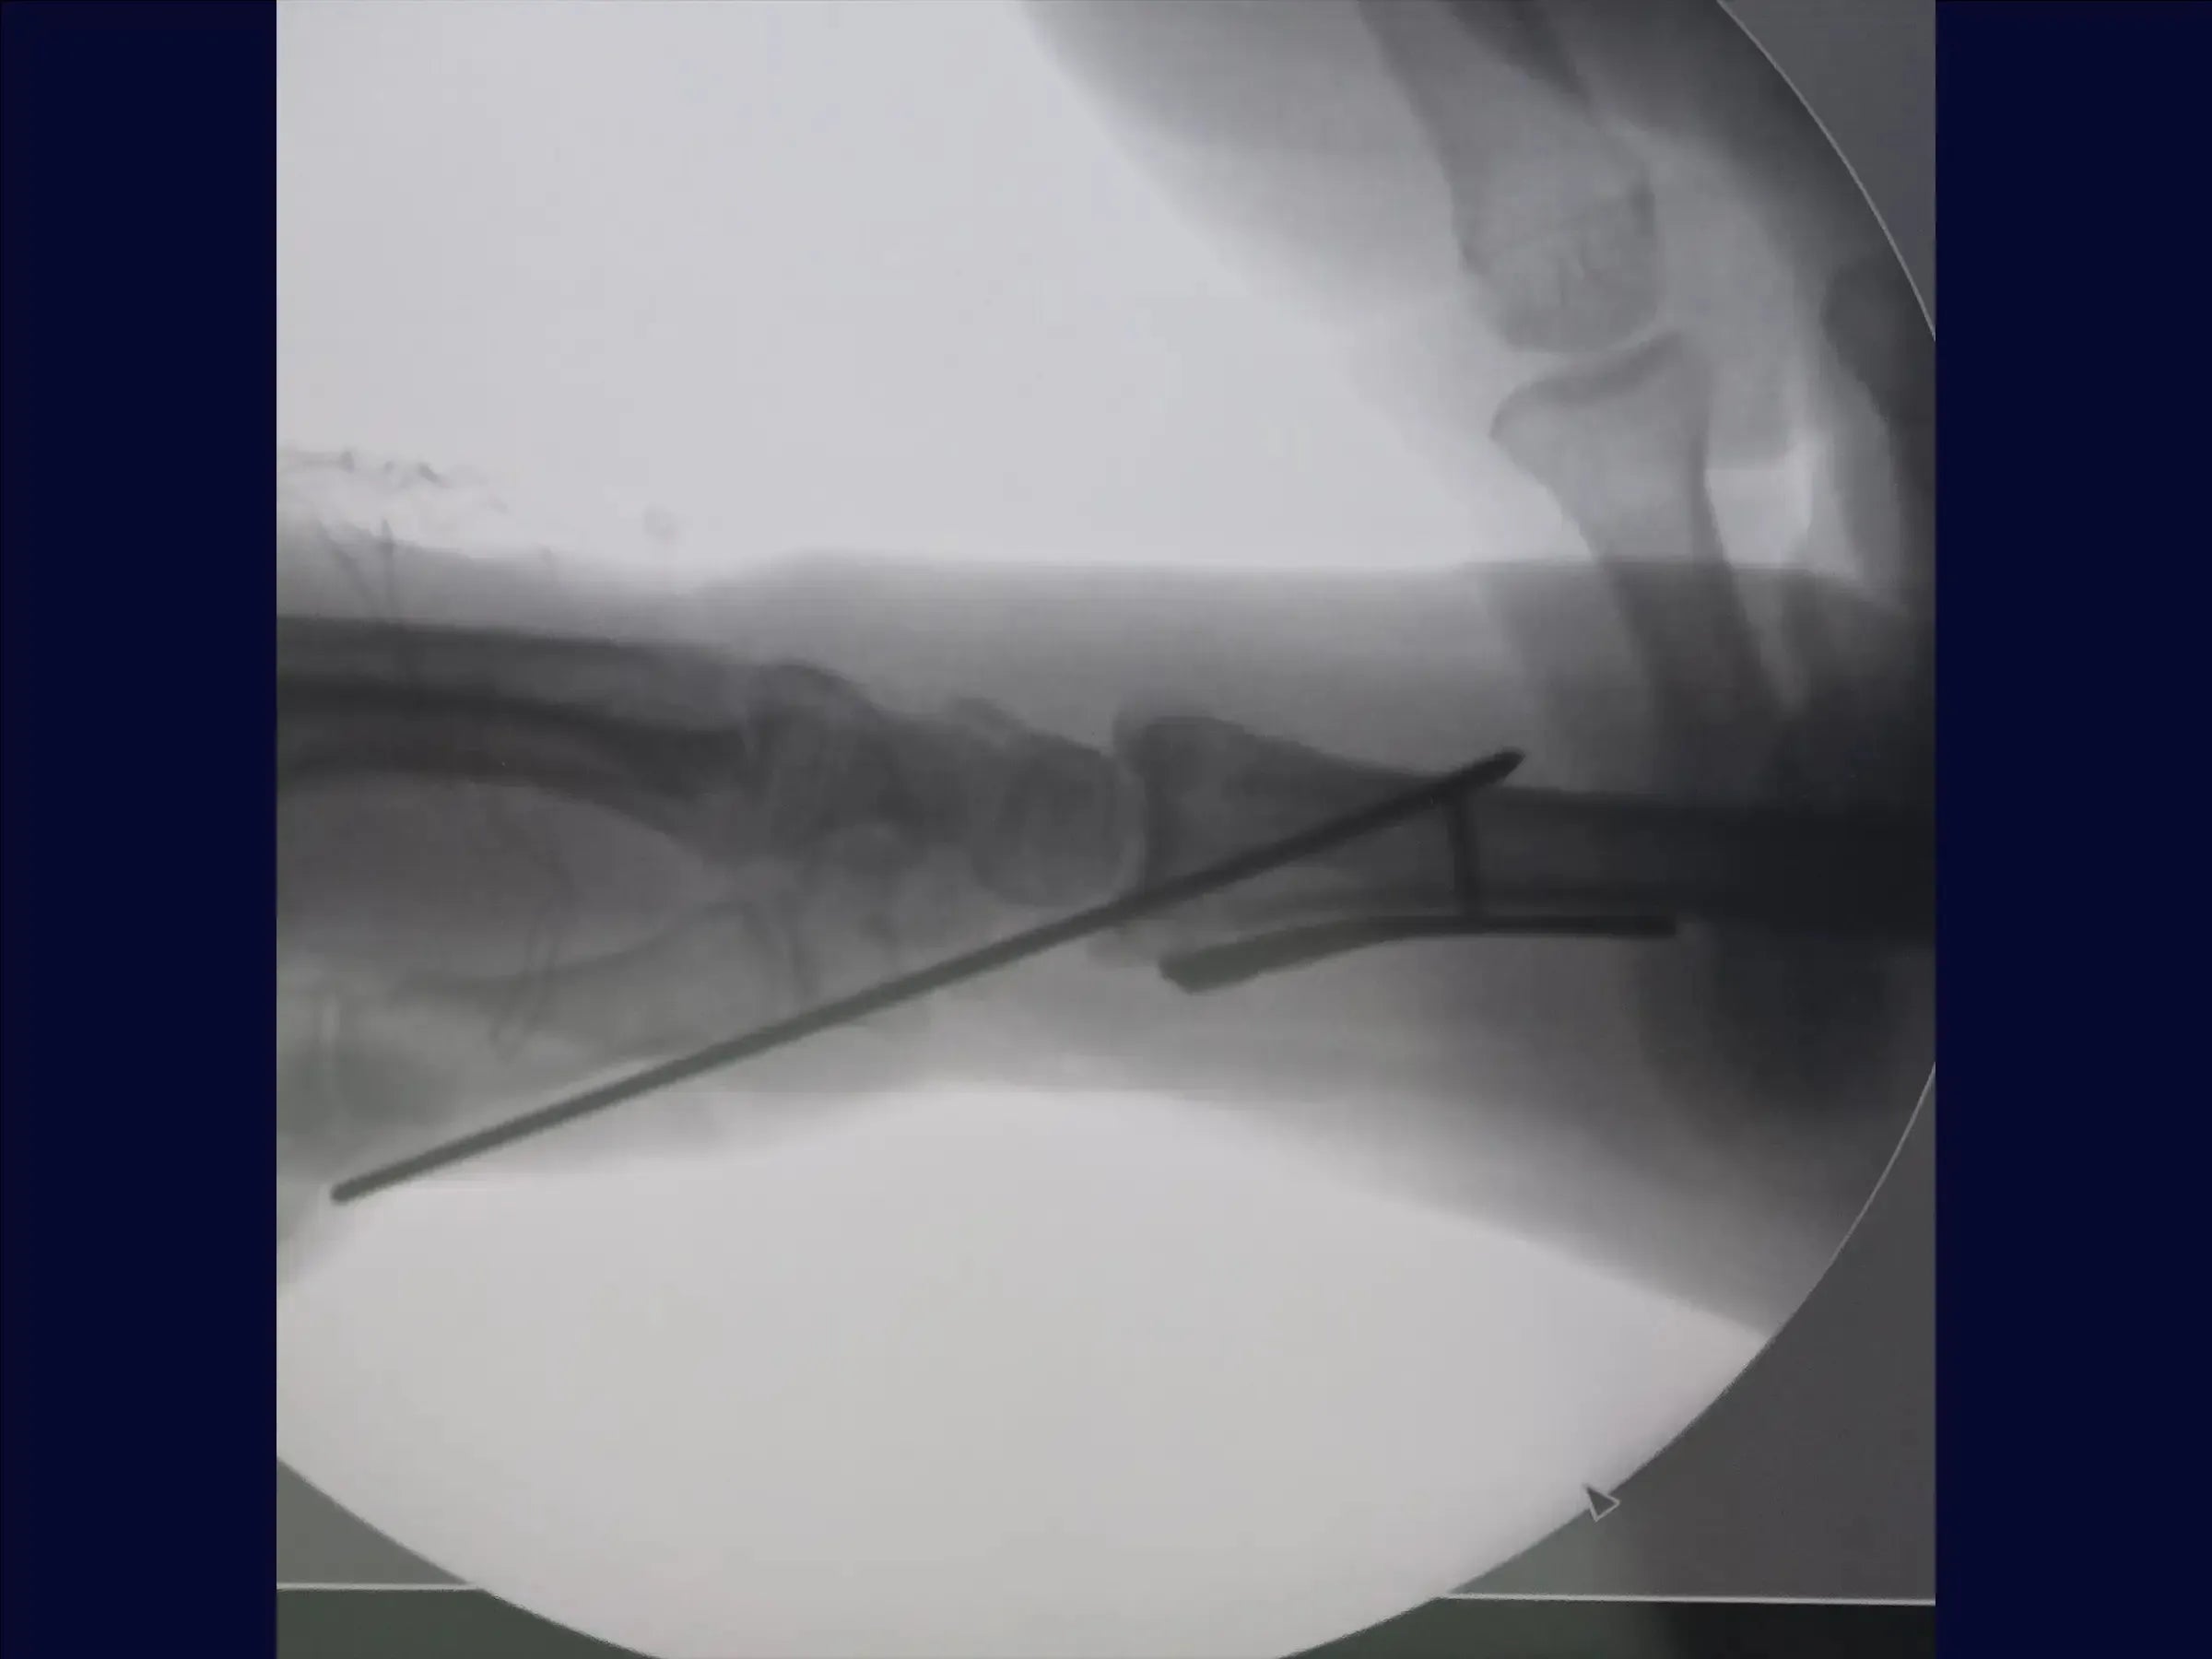

- Fixação Provisória e Avaliação: O treinamento começa com a manobra de redução manual e estabilização provisória com fio de Kirschner de 2.5 mm, visando um bom posicionamento inicial da fratura.

- Exposição do Rádio e Implantação da Placa: O rádio é exposto, e um descolador é utilizado para preparar o leito da placa. Com a fratura já reduzida pela fixação provisória, a colocação dos parafusos deve respeitar a inclinação radial para evitar que fiquem intra-articulares. É recomendado manter a redução manualmente ou usar fios adicionais para evitar perda de redução.